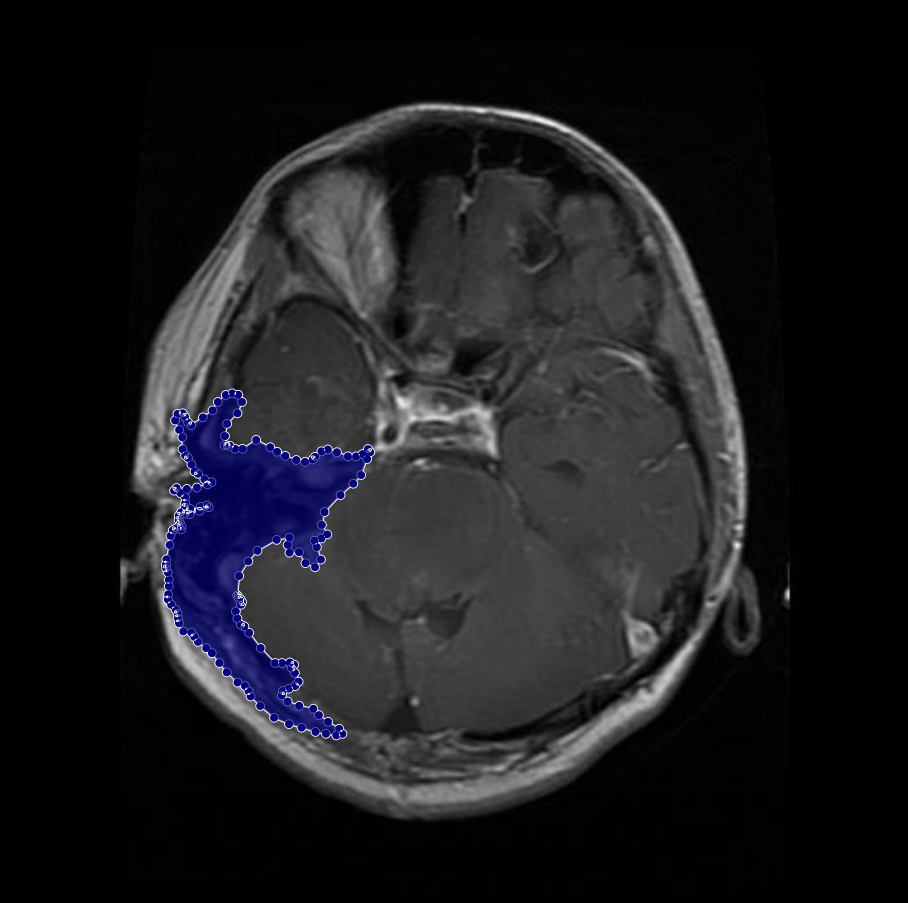

Glioma: Gliomas are irregularly shaped and often infiltrate surrounding tissues, presenting significant challenges for precise boundary definition. These complexities require robust segmentation techniques to capture their variable morphology. As shown in Figure 1, gliomas exhibit irregular and diffuse growth patterns, which are highlighted through annotated tumor masks.

Figure 1: Samples of Glioma segmentation across different imaging planes